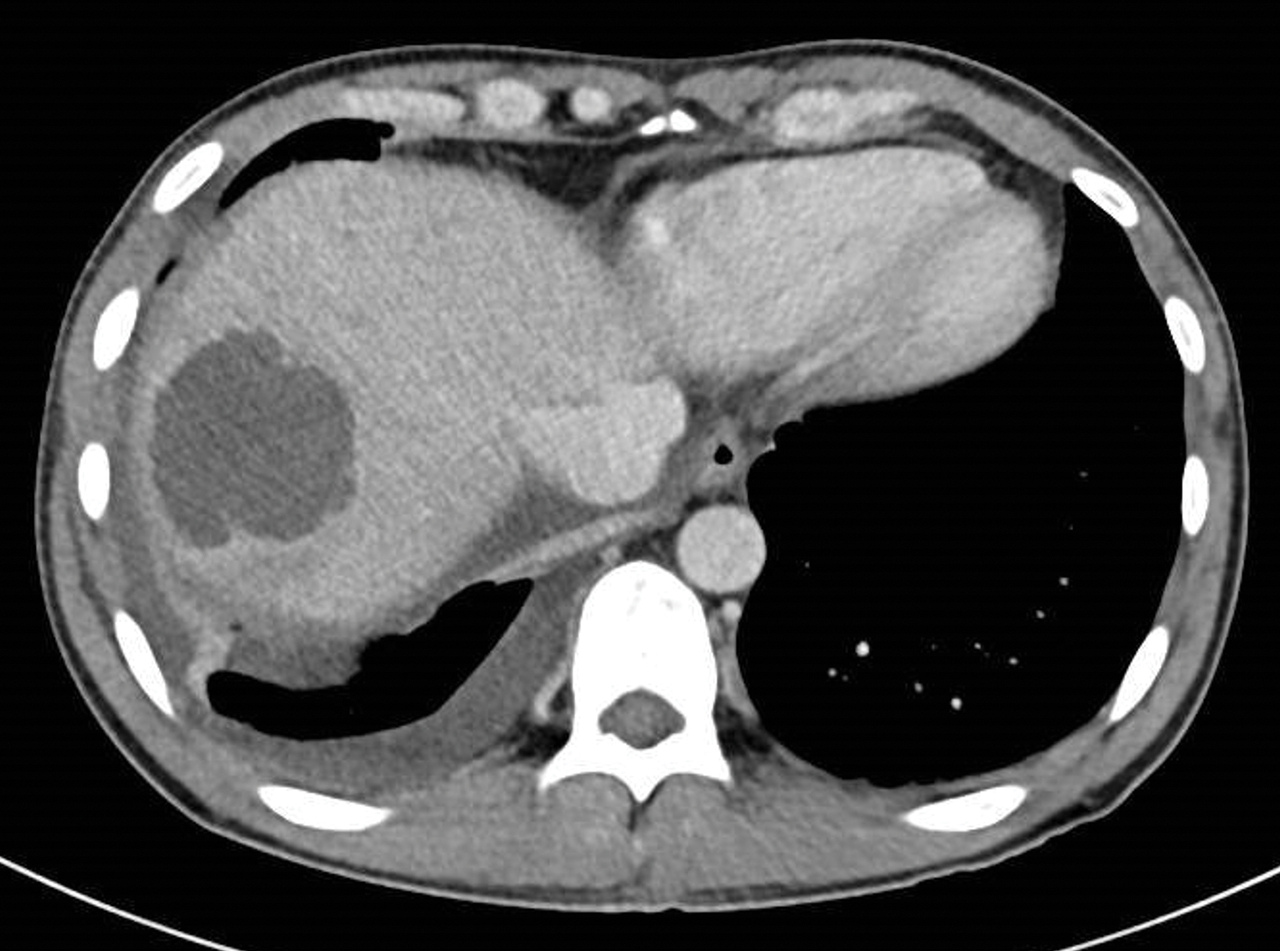

Homme de 35 ans, sans antécédents, ayant des diarrhées depuis 2 mois et n’ayant pas voyagé récemment. Le scanner montre une rectite, une thrombose porte, et une lésion hépatique.

Quel est votre diagnostic ?